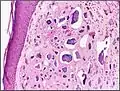

Micrograph of calcinosis cutis. The calcification is purple (bottom of image). H&E stain.

Calcinosis cutis is a type of calcinosis wherein calcium deposits form in the skin. A variety of factors can result in this condition. The most common source is dystrophic calcification, which occurs in soft tissue as a response to injury. In addition, calcinosis is seen in Limited Cutaneous Systemic Sclerosis, also known as CREST syndrome (the "C" in CREST).[1] In dogs, calcinosis cutis is found in young, large breed dogs and is thought to occur after a traumatic injury.